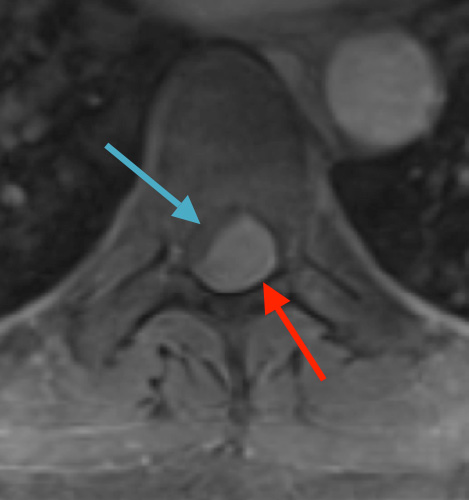

Preoperative MRI T1w demonstrating a large enhancing tumor (red arrow) causing severe cord compression and displacement (blue arrow)